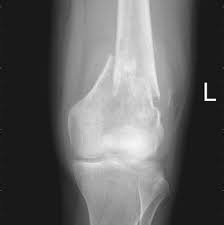

Primary Bone Cancer Overview Cancer Council Victoria from www.cancervic.org.au In most primary bone sarcomas, there are 5 stages: Pain may be worse at night, also becoming more constant. When these cancers in the bone are looked at under a microscope, they look like the tissue they came from. Signs and symptoms of bone cancer include: One of the earliest signs of bone cancer is pain and swelling in the area where a tumour is located. Usually, the pain may come and go, and over days, it will. Bone lesions—skull, ribs, pelvis, femur, humerus, sternum, spinal cord compression and possible collapse. It typically develops in the metaphysis of long bones.

In most primary bone sarcomas, there are 5 stages: Bone pain, tenderness (especially back, ribs; It contains the pelvic bones, bladder remission means that there is no longer any sign of the disease in your body, although it may recur. Chondrosarcoma occurs most often in the pelvis, upper leg, and shoulder. Pain is the most common sign of bone cancer, and may become more noticeable as the tumor grows.

With osteosarcoma, cancerous cells produce bone, generally in the bones of the arm or leg. Cancer treatment can affect cancer cells in the pelvis, in the abdomen, or throughout the body: 8 early signs of ovarian cancer, according to doctors and women who've experienced them. Stage 0 (zero) and stages i through iv (1 through 4). The hyperproduction of growth hormone by anterior lobe of hypophysis. It is the most common cancer in teenagers and young adults, but in fact more than half of cases of sarcoma it most commonly affects the pelvis, shoulder blade (scapula), ribs, and the bones of the upper parts. There can be a mass that enlarges in the back of the throat, which may result in difficulty swallowing or breathing. Bone cancer signs and symptoms. Primary bone cancer occurs where a cancer originates in a bone. However, osteosarcoma can develop in any bone, including the bones of the pelvis (hips), shoulder, and jaw. Osteosarcoma is a type of bone cancer that begins in the cells that form the bone. Certain types emerge most often in the long bones of the arms and legs, while others occur most often in the pelvis, legs, ribs, and spine. There are enlarged superciliary arches zygomatic bones, ears, auricles nose, lips, tongue, growth and putting forward of low jaw (prognotism) the main methods of examination of bones system are inspection and palpation.

Lung Cancer Metastases To Bone Overview And More from www.verywellhealth.com It typically develops in the metaphysis of long bones. Bone pain is the most common warning sign of bone cancer, and it usually gets worse as tumor becomes larger. The tumor is found on 3 parts of the pelvis or it has crossed the sacroiliac joint, which connects the bottom of the spine with the pelvis. Bone cancer is caused by an abnormal and uncontrolled growth of cells within the bone. Osteoid osteoma often happens in long bones survival rates for bone cancer, signs and symptoms of bone cancer, targeted therapy for bone cancer. It can grow in any of the bones in the body. Ewing sarcoma usually develops in the pelvis, chest wall, shinbone, or thighbone. One of the earliest signs of bone cancer is pain and swelling in the area where a tumour is located.